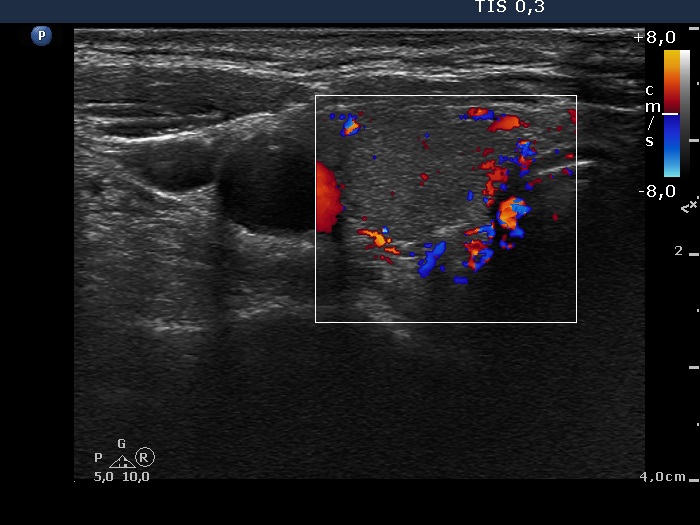

100 consecutive patients with thyroid nodule - Case 27. (ultrasonographic picture 3)

Upper-lateral part of the right lobe, horizontal scan, color Doppler mode. The lesion presents signs of a type 2 vascular pattern.